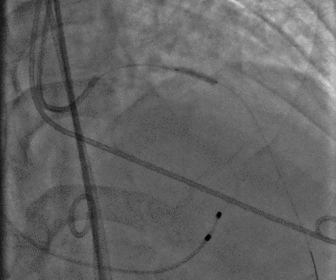

图片

左冠造影

左冠球扩

左冠支架植入

股动脉造影